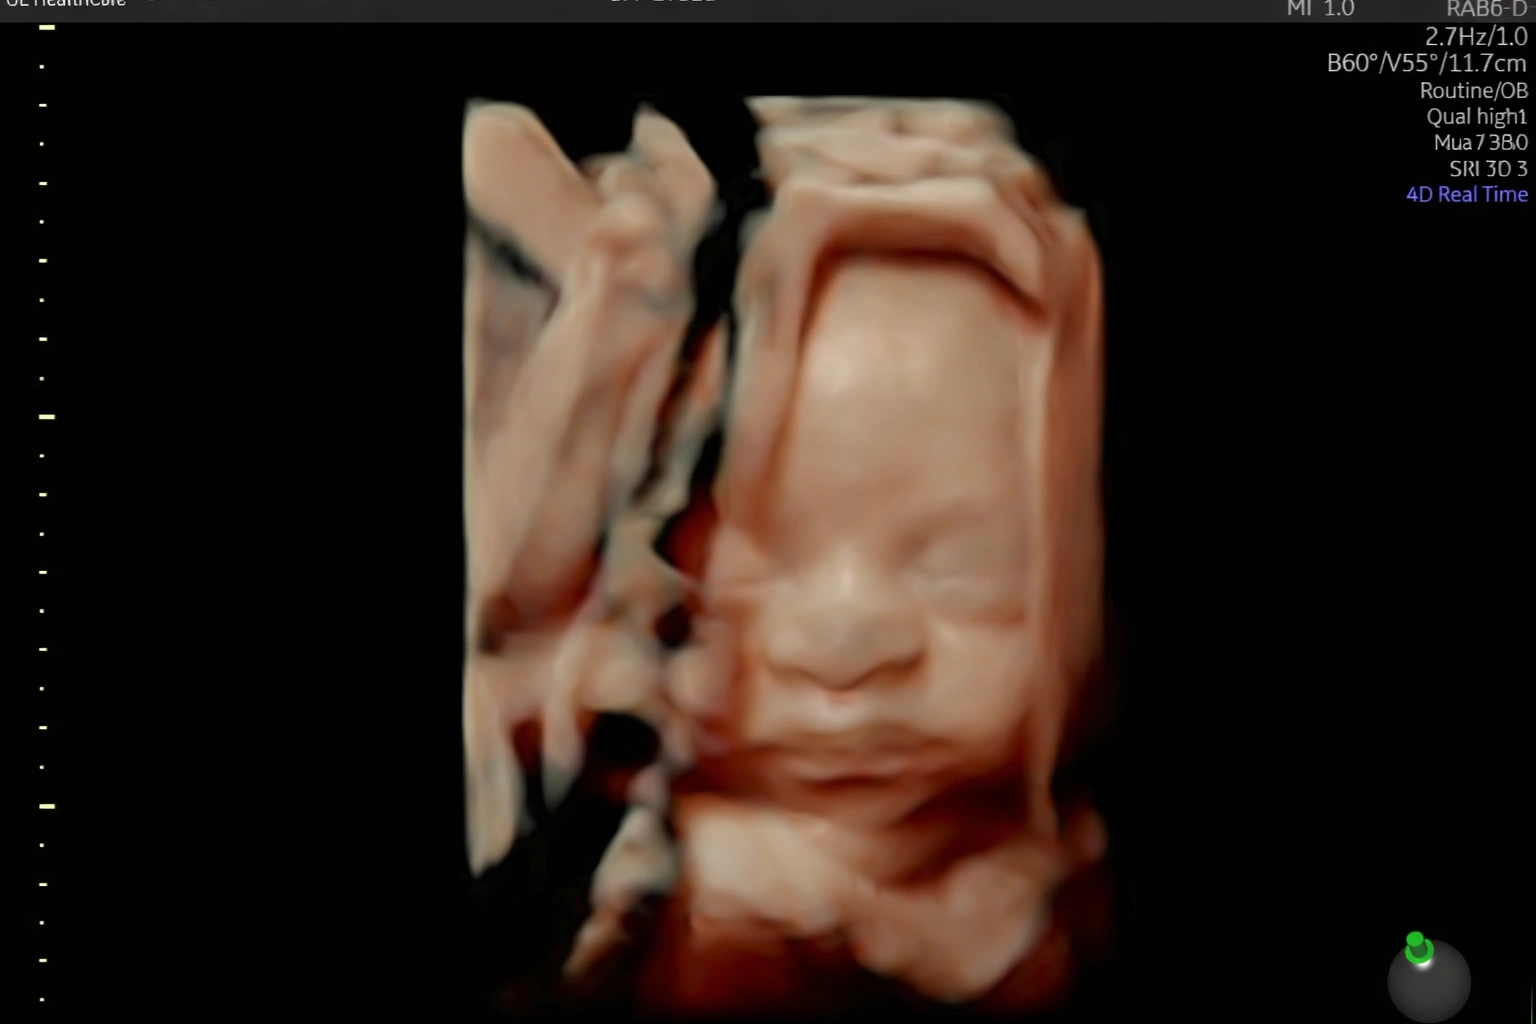

Acompanho detalhadamente toda a evolução do seu bebê ainda na sua barriga.

Realizo diversos tipos de ultrassonografia para garantir que seu bebê chegue ao mundo com saúde.

Estou pronta para realizar diagnósticos precisos sobre como anda a saúde do seu bebê ainda ai dentro da sua barriga. Realizo toda e qualquer tipo de ultrassonografia obstetríca.